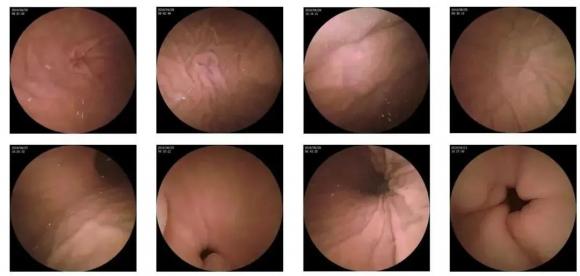

主要表現為食欲減退、惡心、噯氣、胃灼熱、上腹持續或間斷性脹滿,少數患者可發生上消化道出血、消瘦、貧血等情況。 慢性萎縮性胃炎分自身免疫性(A型)和多灶萎縮性(B型)兩種,胃鏡檢查和胃黏膜活檢是最為可靠的診斷方法。

10—15分鐘即可完成賁門、胃底、胃體、胃角、胃竇、幽門等解剖部位觀察,讓胃部檢查更高效。更為重要的是,檢查全程無痛、無創、無麻醉,避免了傳統插管胃鏡帶來的生理痛苦。

二、高清圖像,精確診斷

膠囊機器人的專利三鏡片鏡頭,可深入觀察0.04毫米微小單位,每秒可拍高達4張高清醫學照片。

醫生通過智能閱片系統,可自動對海量圖像識別過濾,智能篩選,能有效提升醫生檢查及閱片效率。

任何細微的胃部病變,如胃潰瘍、胃出血、息肉等都無所遁形,盡在大圣磁控膠囊式內窺鏡系統的掌握之中。